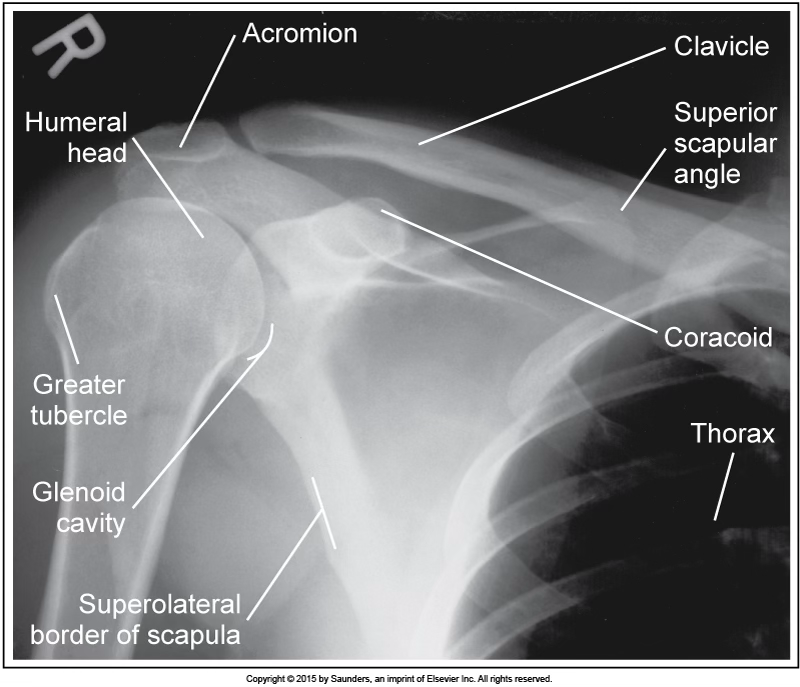

AP neutral shoulder

accurate positioning